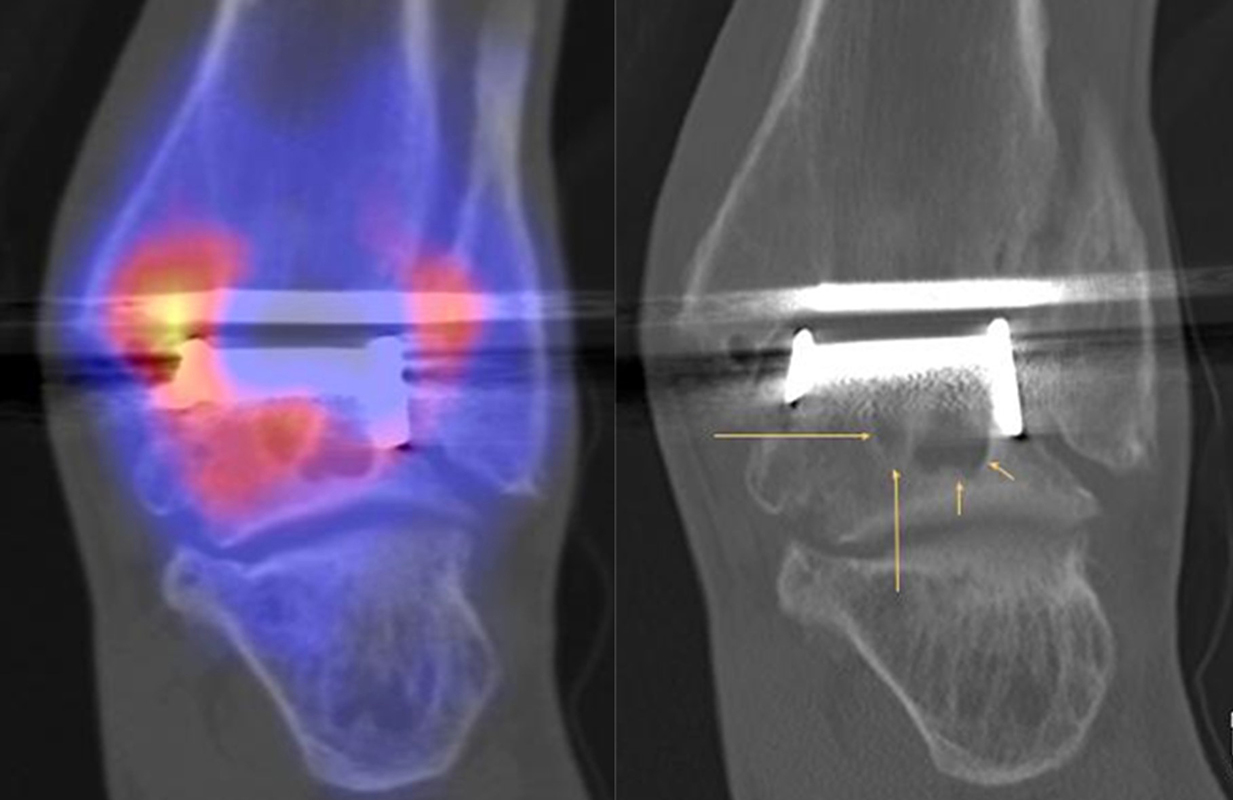

SPECT/CT zur Beurteilung von Endoprothesen

Weltweit nimmt die Prävalenz von Sprunggelenk-Prothesen durch Verbesserungen der Implantate und chirurgischen Techniken zu. Trotzdem berichtet ein signifikanter Anteil von Patienten über persistierende Beschwerden nach Prothesen-Implantation, sodass in der Literatur über Revisionsraten in bis zu 39 % der Fälle berichtet wird 5051. Die Ermittlung der Schmerzquelle mit den konventionellen bildgebenden Verfahren (Röntgen, CT, MRT (auch mit Metall-Artefakt-Reduktion)) ist begrenzt, so dass hier die SPECT/CT die Aussagekraft ähnlich wie bei der Beurteilung anderer Prothesen (z. B. Knie und Hüfte) signifikant erhöht. Verschiedenste Fragestellungen müssen bei der Evaluation einer schmerzhaften Sprunggelenk-Prothese beantwortet werden: Achsenstellung, Prothesenlage, Impingement, Lockerung, Senkung von Prothesenkomponenten, Frakturen, Zysten, Osteolysen, Anschlussarthrosen, Infektionen, Nervenschäden, CRPS, Materialunverträglichkeiten.

Zur Zuordnung von Mehrspeicherungen und morphologischen Veränderungen im Bereich von Prothesen eignen sich folgende Kriterien 51:

• Flächiger starker Fokus am Prothesen-Knochen-Interface → V. a. Lockerung

• Fokus medial oder lateral am Prothesen-Knochen-Interface → V. a. fokaler biomechanischer Stress aufgrund von Fehlstellung der Prothese oder des Rückfußes

• Fokus medial oder lateral im Gelenkabschnitt / Zone zwischen Talus und den Malleolen → Ausdruck eines Impingement

• Im CT zart randsklerosierte rundliche Osteolyse(n) am Prothesen-Knochen-Interface mit metabolischem Fokus → V. a. symptomatische Zyste

• Fokale oder flächige Mehranreicherungen in angrenzenden Gelenken in Verbindung mit arthrotischen Veränderungen im CT → V. a. symptomatische Arthrose

Beispiele für SPECT/CT-Untersuchungen nach OSG-TEP sind in den Abbildungen 6.1. bis 6.3. abgebildet.

Gurbani et al. evaluierten 37 Patienten mit schmerzhaften Sprunggelenkprothesen mit SPECT/CT und korrelierten die Ergebnisse mit klinischen und intraoperativen Befunden. Die SPECT/CT-Ergebnisse korrelierten zu 89,2 % (33/37 Pat.) mit der definitiven Diagnose. 28 Patienten wurden operativ revidiert und der Vergleich der SPECT/CT-Befunde mit den intraoperativen ergab eine Übereinstimmung von 92,9 % (26/28 Pat.). Die SPECT/CT identifizierte in den meisten Fällen aseptische Lockerungen (12/33 Pat.) und Impingement (11/33 Pat.). Seltenere Diagnosen waren Fehlstellungen (4/33 Pat.), Zystenbildungen (2/33 Pat.), subtalare Arthrosen (2/33 Pat.) und Infektionen (2/33 Pat.) 51.

Die Autoren beschreiben einen Fall, der neben einem Fokus am lateralen Malleolus auch eine starke flächige Anreicherung am talaren Prothesen-Knochen-Interface 17 Monate nach TEP-Implantation aufwies, so dass neben dem Verdacht auf ein laterales Impingement auch der Verdacht auf eine Lockerung der talaren Prothesenkomponente geäußert wurde. Intraoperativ bestätigte sich die Lockerung der talaren Prothesenkomponente nicht, sondern nur das laterale Impingement, welches mittels Debridement erfolgreich therapiert wurde 51. Da der Pat. bereits vor der TEP-Implantation eine Triple-Arthrodese erhalten hatte (welche im SPECT/CT unauffällig war), kann eine solche flächige Mehrspeicherung auch als weitgehend asymptomatische Stressreaktion gewertet werden.

Mertens et al. 52 berichten unter Anwendung eines standardisierten Auswerte-Schemas über eine Treffsicherheit von 96 % (Sensitivität 100 %, Spezifität 80 %) des SPECT/CT zur Diagnose der Ursachen für eine schmerzhafte Sprunggelenkprothese (n=24). Der SPECT/CT-Befund führte in 86 % zu einer spezifischen Therapie, welche in 83 % der Fälle zum Therapieerfolg führte.

Eine Analyse von Mason et al. 53 von 14 Patienten mit schmerzhaften Sprunggelenksprothesen, welche mittels SPECT/CT untersucht wurden, fanden in 13/14 Patienten ein SPECT/CT-Korrelat für die Beschwerden, wobei bei 12 Patienten der Fokus talar medial lokalisiert war. 8 Patienten wurden operativ revidiert und der Fokus entsprach einer verminderten bzw. fehlenden ossären Integration der talaren Prothesen-Komponente.